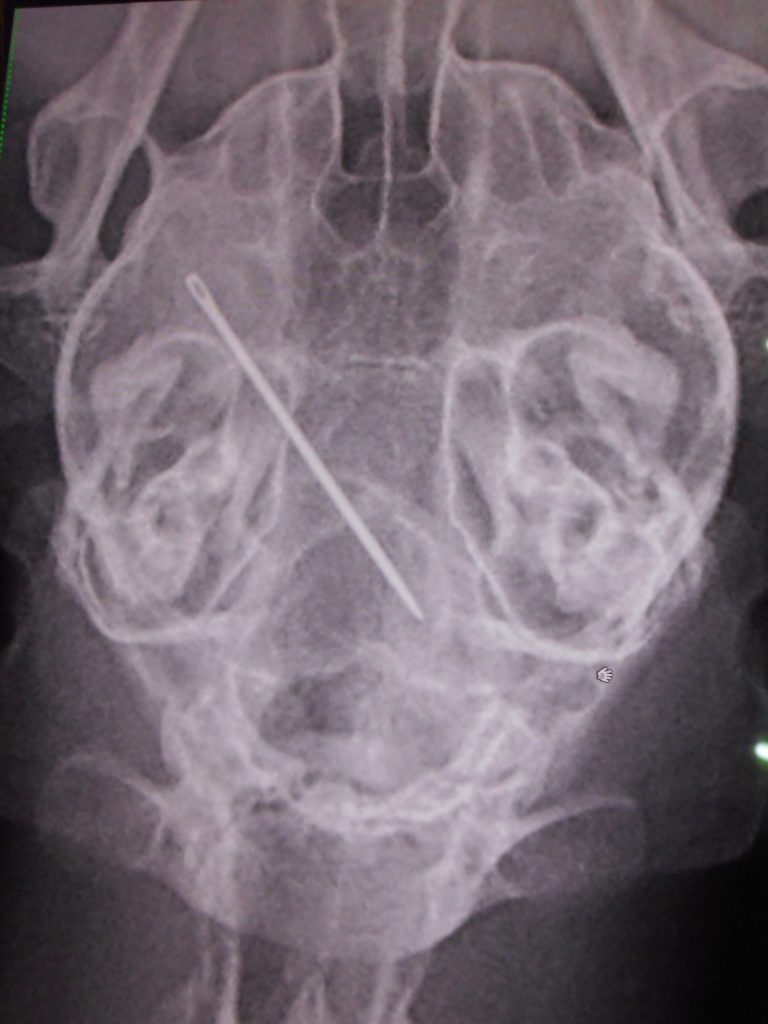

縫い針飲み込んだという主訴です

まずは、レントゲン検査

💦

下手に動くとやばいところに刺さりそう

他にもないか全身のレントゲン検査

結果、この1本勝負